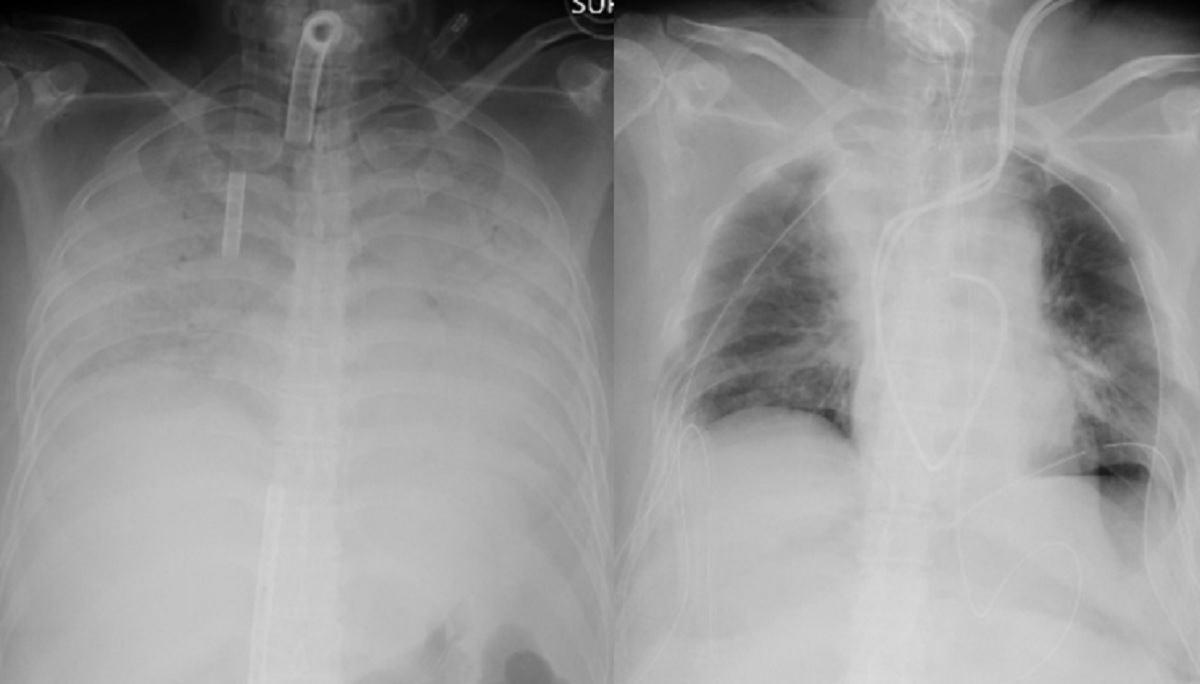

বিশ্বে প্রথমবারের মতো জীবিত ব্যক্তির দেহ থেকে ফুসফুস প্রতিস্থাপনের ঘটনা ঘটেছে। করোনাভাইরাস নিয়ে দুনিয়াজুড়ে উদ্বেগের মধ্যেই চিকিৎসা ক্ষেত্রে বড় ধরনের এই সাফল্য পেয়েছে জাপান।

সিএনএন জানিয়েছে, করোনাভাইরাসে ফুসফুস ক্ষতিগ্রস্ত হওয়া এক নারীর শরীরে তার স্বামী এবং সন্তানের ফুসফুস প্রতিস্থাপন করা হয়েছে। চিকিৎসা বিজ্ঞানে ফুসফুস প্রতিস্থাপনের ঘটনা এর আগেও ঘটেছে। তবে ব্যতিক্রম হচ্ছে জাপানের এ ঘটনায় জীবন্ত ব্যক্তির ফুসফুস করোনা আক্রান্ত রোগীর দেহে প্রতিস্থাপন করা হয়েছে।

জাপানের কোয়োটা ইউনিভার্সিটি হাসপাতাল কর্তৃপক্ষ জানায়, সম্প্রতি ওই নারীর শরীরে করোনা সংক্রমণের ফলে তার ফুসফুস দুটি মারাত্মকভাবে ক্ষতিগ্রস্ত হয়। এতে তার বেঁচে থাকার সম্ভাবনা ক্ষীণ হয়ে পড়ে। পরে এই হাসপাতালের চিকিৎসকরা সিদ্ধান্ত নিয়ে ওই নারীর স্বামী ও ছেলের সুস্থ ফুসফুস তার দেহে প্রতিস্থাপন করতে সফল হন। ৩০ জন বিশেষজ্ঞ চিকিৎসকের জটিল এই অস্ত্রোপচার করতে সময় লেগেছে প্রায় ১১ ঘণ্টা।

হাসপাতাল কর্তৃপক্ষ জানিয়েছে, ডোনার জীবিত অবস্থায় সফল ফুসফুস প্রতিস্থাপনের ঘটনা বিশ্বের ইতিহাসে এটাই প্রথম। ফুসফুস প্রতিস্থাপনের এই পুরো অপারেশন যার নেতৃত্বে হয়েছে তার নাম ড. হিরোশি ডেট।

করোনার ফলে ওই নারীর নিউমোনিয়া হয়ে গিয়েছিল। তবে সফল অপারেশনের পর ড. হিরোশি এখন আশা করছেন দ্রুত সুস্থ হয়ে উঠবেন ওই নারী।